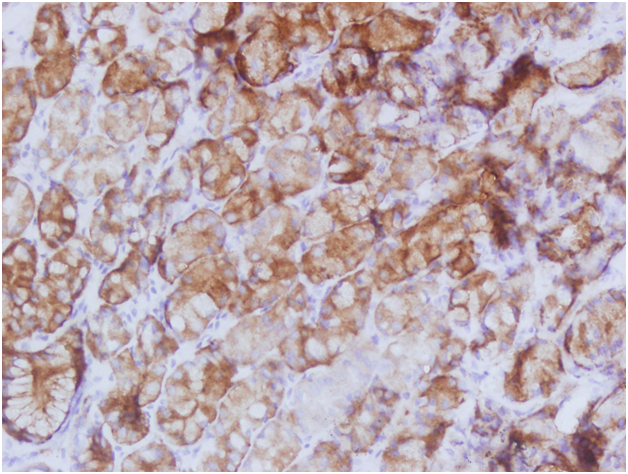

Regarding IHC staining for HPV 16 and 18, positive findings were revealed in 13/100 (13%) and couldn't be disclosed in 87 (87%) of the study subjects, hence, none of the cases was identified with HPV18 (confirmed by PCR), as shown in Microphotograph 1 & 2. The risk associated with HPV 16 as etiological factor for esophageal cancer and the Odd Ratio (RO) and the 95% confidence interval was 31(1.81-528), P <0.017. Of the 54 males with esophageal cancer, 7/54 (12.9%) were identified with HPV16 infection and the remaining 47/54(87.1%) found without HPV16 infection. Of the 45 females with esophageal cancer, 6/45(13.3%) were found positive for HPV 16 immunostaining and the remaining 39/45(86.7 %) were found negative for HPV16.

Microphotograph 1 Esophageal carcinoma showing positive HPV16 expression (Immunohistochemical staining using C1P5 antibody), En Vision_ System HRP. X100.

Microphotograph 2 Esophageal carcinoma showing positive HPV16 expression (Immunohistochemical staining using C1P5 antibody), En Vision_ System HRP. X400.